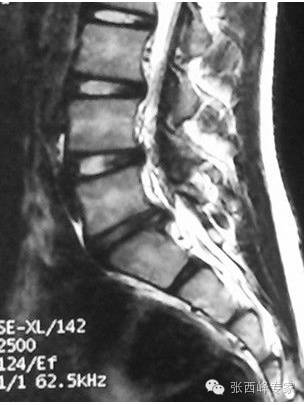

核磁矢状位腰5骶1椎间盘突出